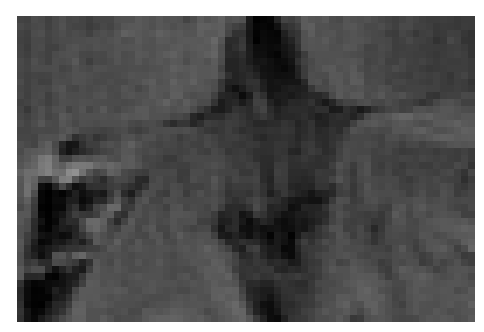

(e) NPB-REC Std.

Figure 6: Examples of reconstruction results. Rows 1, 3, and 5: The reference (GT) fully sampled image, the reconstructed images obtained by the three models (1-3), NPB-REC, baseline, E2E-VarNet trained with Dropout, and the Std. map derived from our method for example from the knee dataset, the brain dataset, and the brain dataset sampled with radial mask L=50𝐿50L=50, respectively. Rows 2, 4, and 6: The corresponding annotated ROIs of the cartilage, edema, and nonspecific white matter lesion respectively.

Fig. 6 depicts the reconstruction results obtained by (1) our NPB-REC approach, (2) the baseline, and (3) Monte Carlo Dropout, for examples of both the knee (row 1) and the brain (rows 3 and 5) datasets. The first two examples were obtained by the models that trained on brain data and were tested on knee data (row 1) and vice versa (row 3). In knee images, all three models exhibit minimal differences in handling pronounced folding artifacts. However, our approach demonstrates superior reconstruction performance for anatomical annotations or pathological regions, labeled by radiologists, in terms of both PSNR and SSIM. The last example is a reconstructed brain image that was obtained by the three models, where the k-space input is undersampled by a radial mask with L=50𝐿50L=50. Table 2 presents the mean PSNR and SSIM metrics, calculated over the whole inference knee dataset, for the three models that were trained on brain data. The NPB-REC method shows a considerable improvement in the generalization ability on knee data for higher acceleration rates R=8𝑅8R=8 and R=12𝑅12R=12 in both annotation regions and the whole images. However, both the baseline and Dropout methods show a slight improvement in the metrics in the case of a small acceleration rate R=4𝑅4R=4. Table 3 shows the results of the inverse experiment, i.e. calculating the mean PSNR and SSIM metrics over the whole brain inference set for the three models that were trained on knee data only. The generalization capability of the three models in the case of an anatomical distribution shift from the knee to the brain is better than the opposite scenario. This is not only measured quantitatively by the SSIM and PSNR metrics, but also visible in the predicted reconstructions. For instance, the brain MRI reconstructed images exhibit fewer artifacts than the produced knee images, as shown in row 1 vs. row 3 in Fig. 6.

Table 3 presents the mean PSNR and SSIM metrics calculated over the whole inference knee dataset that were obtained by the three models, where the k-space input is undersampled by a radial mask with L=50𝐿50L=50 and L=40𝐿40L=40. Although the NPB-REC approach improves the accuracy of reconstruction when the metrics are measured on the whole image, it doesn’t yield the best performance on the annotation ROIs. However, it is still able to reconstruct high-quality images while preserving the important anatomical content in these annotations. This can be clearly observed in the last row in Fig. 6, where the topmost part of the ROI image predicted by NPB-REC is preserved, in contrast to the other benchmarks.